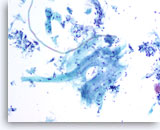

Lubricant B treated vial

…shows the effect of excessive lubricant.The field of view has sparse cellularity with an increase in the amount open spaces. In this instance, the excessive lubricant interfered with the cell collection process during slide preparation.

10x

Lubricant B treated vial

…shows the effect of excessive lubricant. The field of view has sparse cellularity with an increase in the amount open spaces. In this instance, the excessive lubricant interfered with the cell collection process during slide preparation.

10x